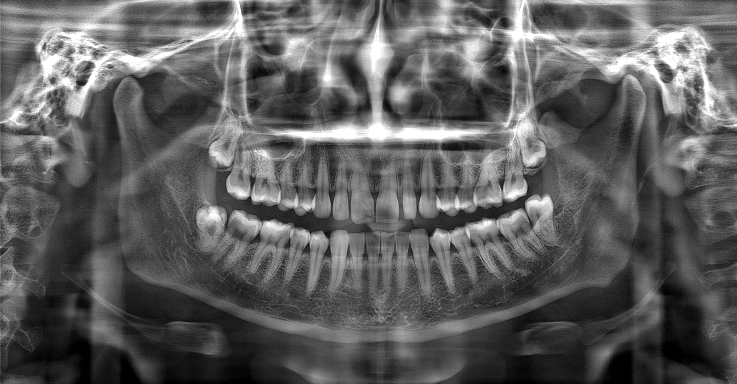

▲“ "The Effect of 'PD' Technology in Panoramic Images"

▲From left to right: Original Image, Mainstream Algorithm, "PD" Technology

▲Advantages of "PD" Technology: Deep Restoration of Image Details